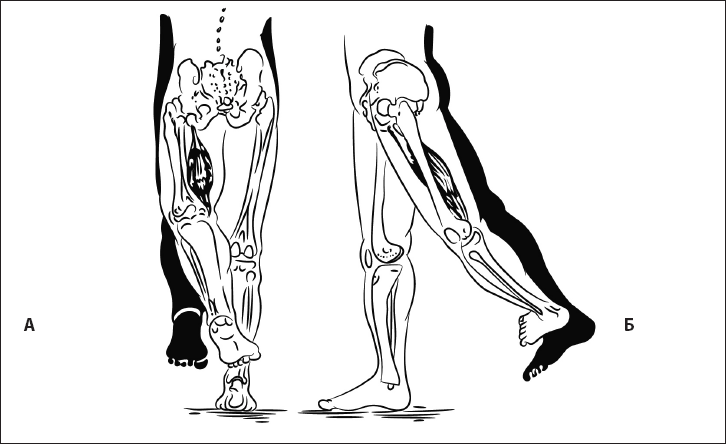

Рис. 38. Экстензия бедра с укорочением пояснично-подвздошной мышцы. А – вид сзади, Б – вид сбоку.

Ошибка 2. Вместо сгибания в тазобедренном суставе происходит сгибание в коленном или поясничном регионе; пальцы стопы относительно пятки смещаются вовнутрь. Причина – гипотония пояснично-подвздошной мышцы (рис. 39).

Ошибка 3. Сгибание ноги сопровождается разворотом таза.

Рис. 39. Гипотония пояснично-подвздошной мышцы. А – вид спереди, Б – вид сбоку, В – вид сзади.